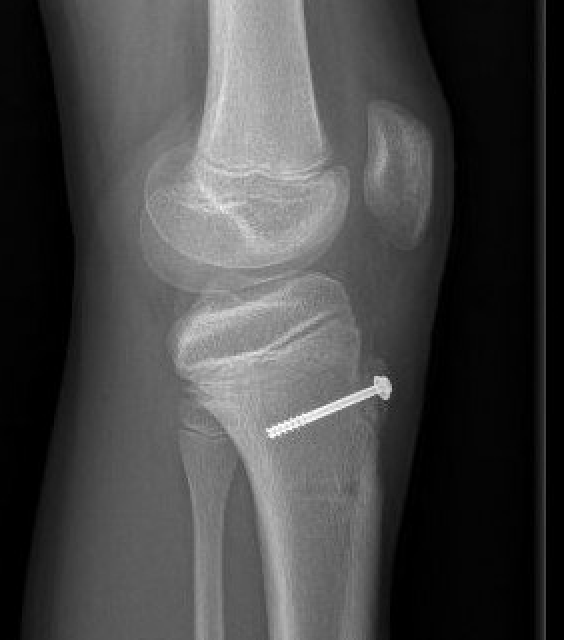

Type I /Type II

Screw +/- anchor fixation +/- tension band fixation of tibial tubercle and patella tendon

- screw +/- washer in fragment if large

- can supplement with Krackow sutures in patella tendon and fixed distally with suture anchors